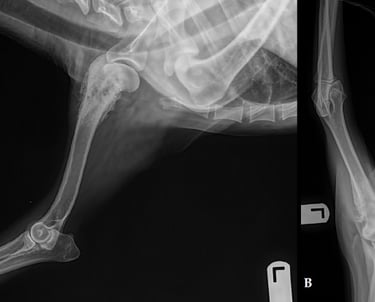

Fracturas complejas

Solución ideal para fracturas con múltiples fragmentos o alta inestabilidad.